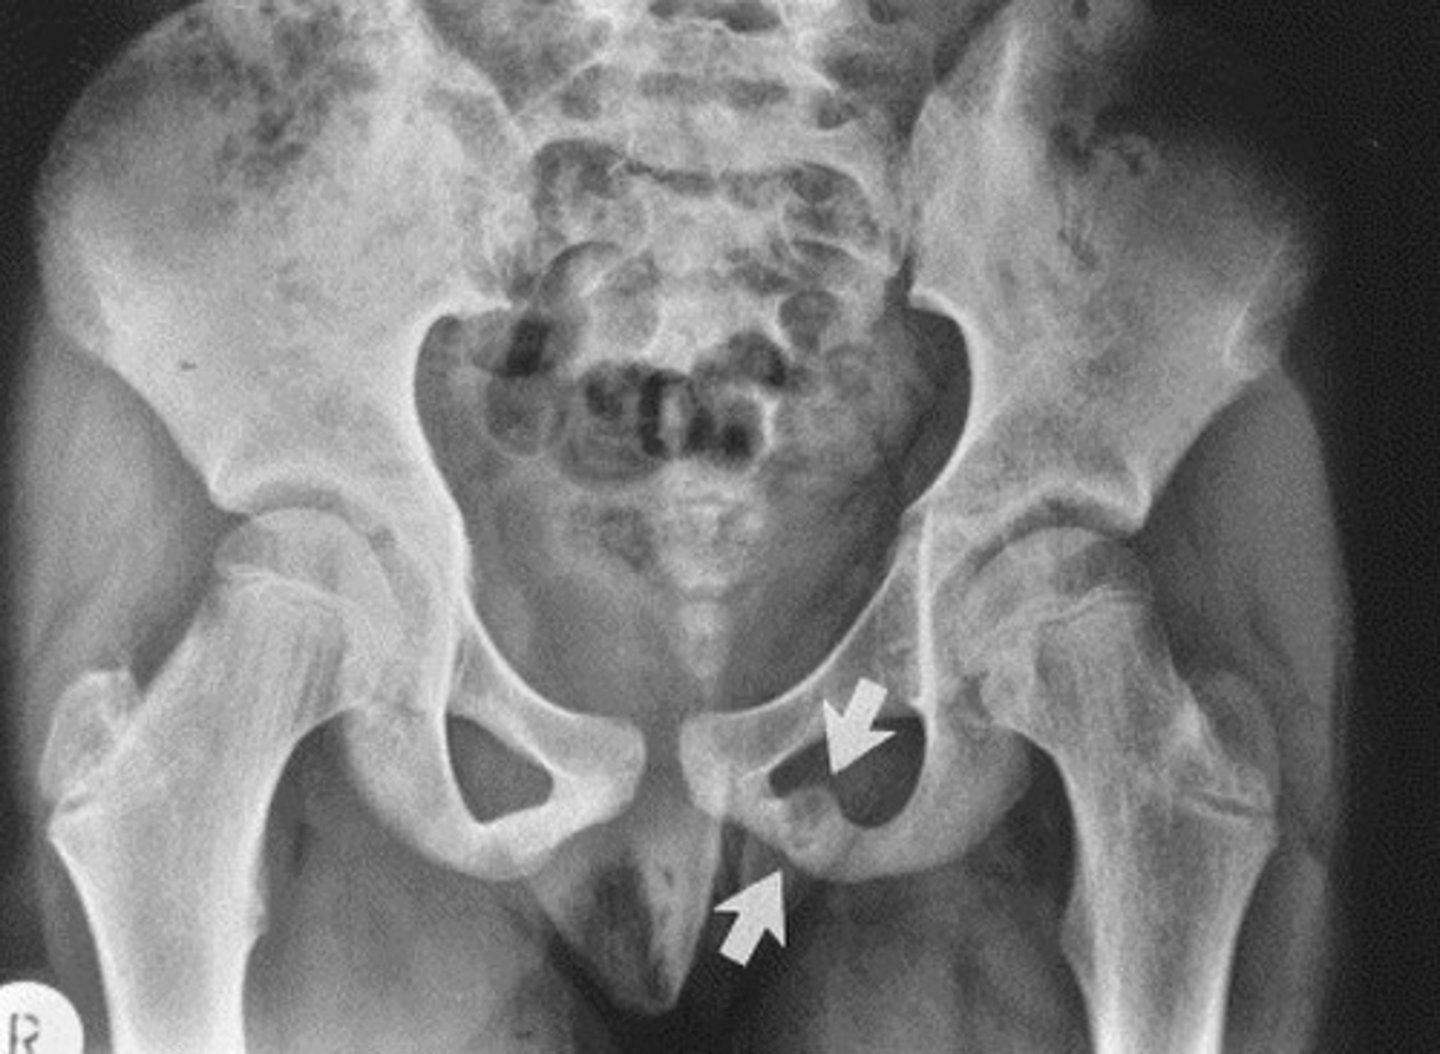

Putti's Triad

Sign of DDH

(1) Absent or small proximal femoral epiphysis

(2) Superolateral or lateral displacement of the femur

(3) Increased acetabular angle